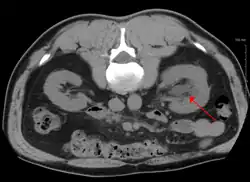

CT scan of bilateral hydronephrosis due to a bladder cancer -